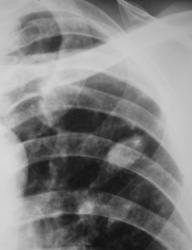

Туберкулома верхней доли левого лёгкого в фазе распада.

Пациент, находящийся на учёте в туб. кабинете, направлен на плановое рентгенологическое исследование с целью динамического наблюдения.

На обзорной рентгенограмме органов грудной полости, произведенной в прямой стандартной проекции, справа на верхушке определяются отдельные, средних размеров очаги.

Слева (иллюстрация 1) определяется некоторое снижение прозрачности верхушки за счет нежного фиброза, на фоне чего дифференцируются отдельные очаги средней интенсивности. Во 2 межреберье определяется овальной формы фокусная тень неоднородной структуры, с очаговыми уплотнениями и вкраплениями извести, с эксцентричным просветлением, с нечеткими контурами. От данной фокусной тени к корню левого лёгкого визуализируется «дорожка». Несколько каудальнее и латеральнее, указанной фокусной тени, в 3 межреберье определяются мелкие кольцевидные структуры по типу кавернизировавшихся очагов.

Иллюстрации 2, 3. Фрагменты рентгенограммы с увеличением. Четко определяется неоднородность структуры фокусной тени, с нечеткостью контура, с наличием эксцентрически расположенной полостью распада.

Иллюстрации 4, 5. Фрагмент рентгенограммы – 3 межреберье – очаги в фазе кавернизации.